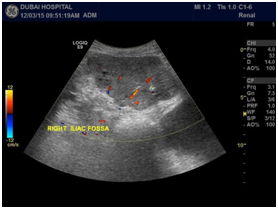

Over a few months, he was complaining of intermittent haematuria with a bulge noticed at the right lower loin, Ultrasound was done in April 2015; and revealed a big mass in the right old transplant kidney (see image 1A, 1B). CT scan with contrast was done (image 2A, 2B), and revealed a large lobulated outlines heterogeneously enhancing mass arising from the right iliac fossa of the transplanted kidney (measures 8.7x 6.9x11.5cm in diameter) with local invasion, lungs metastasis and right common iliac vein tumor thrombus. Due to above finding patient underwent right allograft nephrectomy, with uneventful post-operative course. Biopsy of the transplanted kidney consists with clear renal cell carcinoma. His immunosuppression had been modulated by stopping Mycophenolate and replacing cyclosporine by Everolimus. He is also under oncology follow up (Figure 1a,1b & 2a,2b).

Figure 1a&1b: Old Transplanted kidney in the right iliac fossa shows a large hypoechoeic solid lobulated mass measuring 10.0x6.9cm with increased vascularity on Doppler.